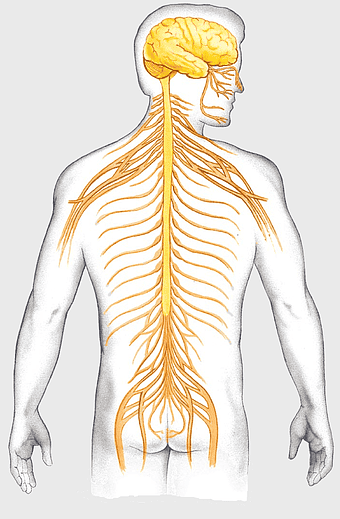

blue human anatomy illustration, human circulatory system diagram, digital human skeleton image, electric blue medical figure, human nervous system visualization, human body organ map, human health care graphic -

human skeleton, bone structure, nervous system anatomy, joint function, skeletal framework, anatomical illustration, human body composition -

Central nervous system diagram, human spinal cord anatomy, vertebral column illustration, brain and neuron structure, nervous system pathway, human body medical art, peripheral nerve network -